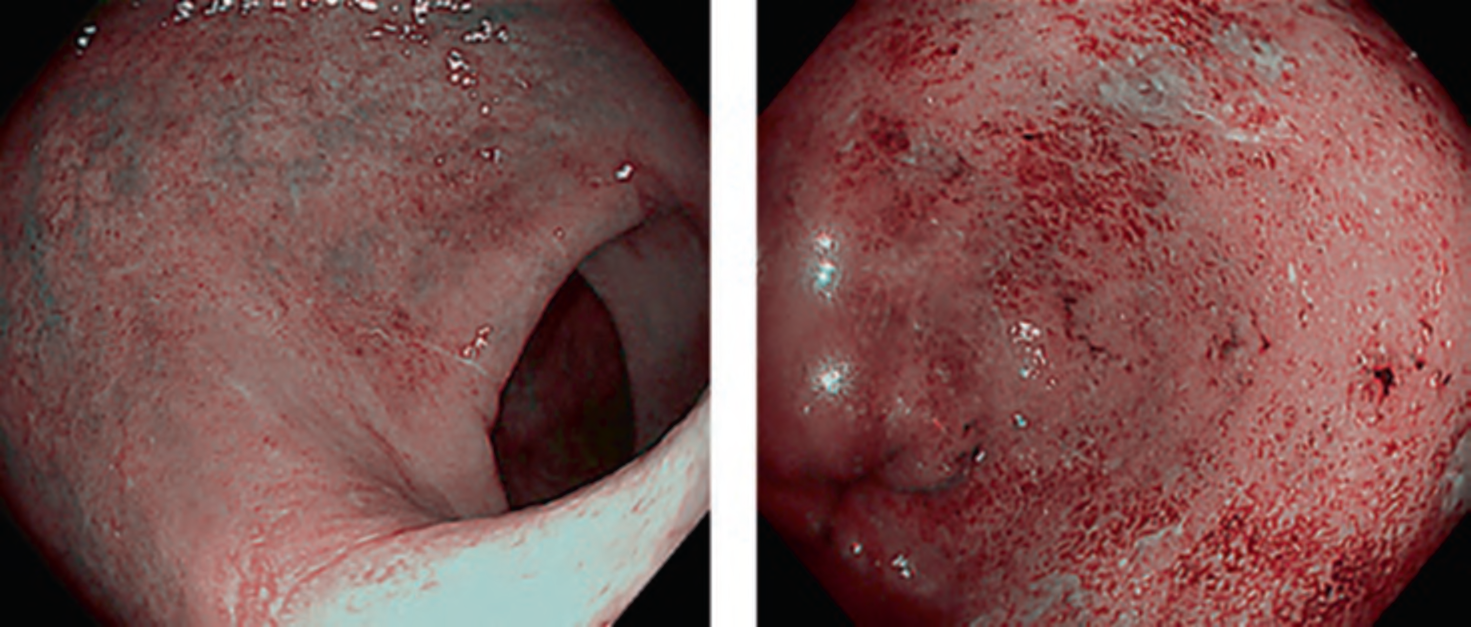

In this mode, deep blood vessels are displayed in green and superficial blood vessels in red. Images obtained by this mode are similar to those by narrowband imaging; however, bile in the digestive tract lumen does not turn red, facilitating mucosal observation in colonoscopy with poor preparation. It is also reported that this mode enables to visualize subtle inflammatory activity that is unable to find in white light imaging in patients with ulcerative colitis (. Fig. 8) [9].

Fig. 8 White light imaging versus RDI mode 3 in cases with ulcerative colitis. a White light imaging of case with Mayo score 0. b RDI mode 3 of case with Mayo score 0. c White light imaging of case with Mayo score 1. d RDI mode 3 of case with Mayo score 1. e White light imaging of case with Mayo score 2. f RDI mode 3 of case with Mayo score 2.

Fig. 8 (continued) g White light imaging of case with Mayo score 3. h RDI mode 3 of case with Mayo score 3